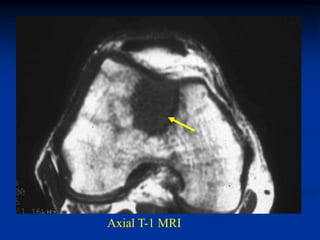

Axal T-1 MRI

Axial T-2 MRI